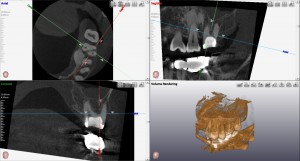

左上のCT像をみるとパーフォレーションの大きさがよく分かります。

右上のCT像で、遠心根の病巣の大きさが良く分かります。

CTは超便利です。